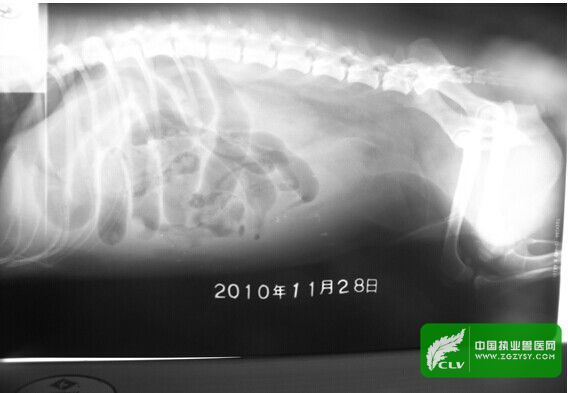

2.2X光摄片检查(腹部右侧位):腹部膨大,广泛性密度增大,影像模糊,腹腔内脏器官轮廓不清,可见充气肠袢的低密度阴影,肠管浆膜结构消失。